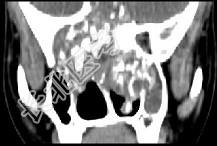

- 多项选择题男性,28岁, 因鼻塞、头痛1年余,鼻窦CT扫描如图所示, 请选择正确的描述与结论 ( )

A、双侧上颌窦、筛窦、鼻腔及蝶窦内见软组织肿块影

B、肿块内密度不均,有较多致密钙化影

C、窦壁及颅底骨质破坏